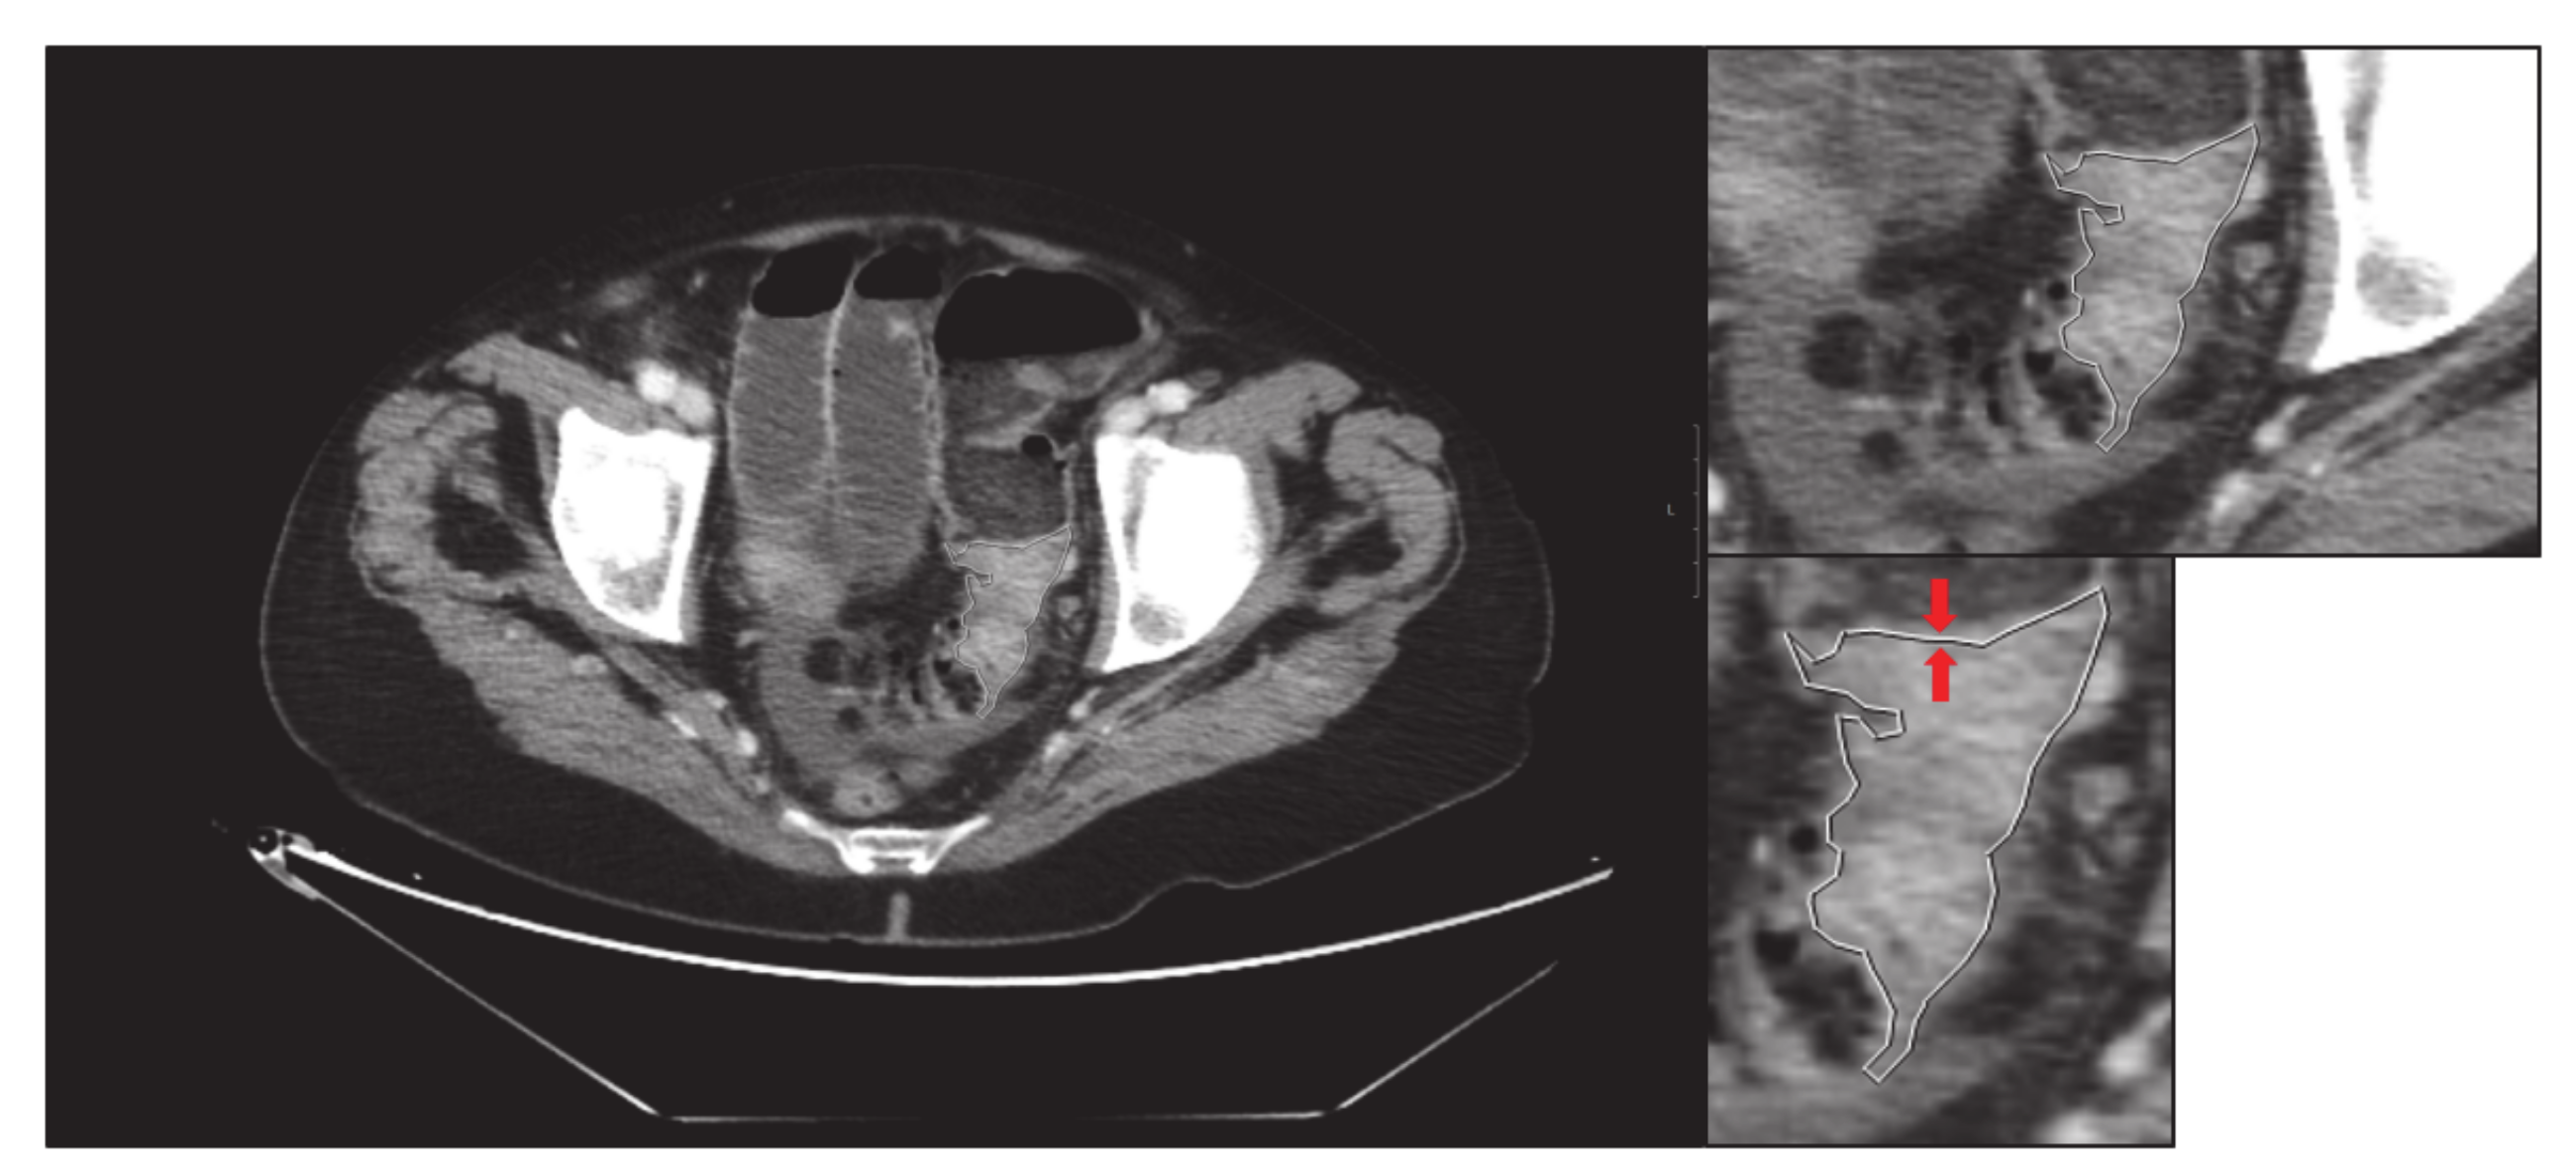

- Secondly, an expert radiologist delimits the tumour, and an image of the delimited tumour is saved in its original size: “large-delimited.tiff” (i.e., Figure 2). The delimitation process is carried out manually by an expert, since due to the morphological heterogeneity of the tumour it is impossible to make an automatic delimitation.